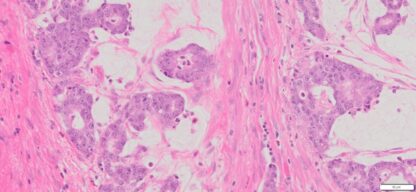

| Tissue | Pathology Diagnosis | Gender/ Age (year) | %Tumor Area | Tumor Grade | TMN/Stage | IHC data | |

| Appendix | Human Appendix Mucinous Adenocarcinoma | Male/68 | 10% | II |

|

MLH1,2,and 6, PMS2 show intact nuclear expression |